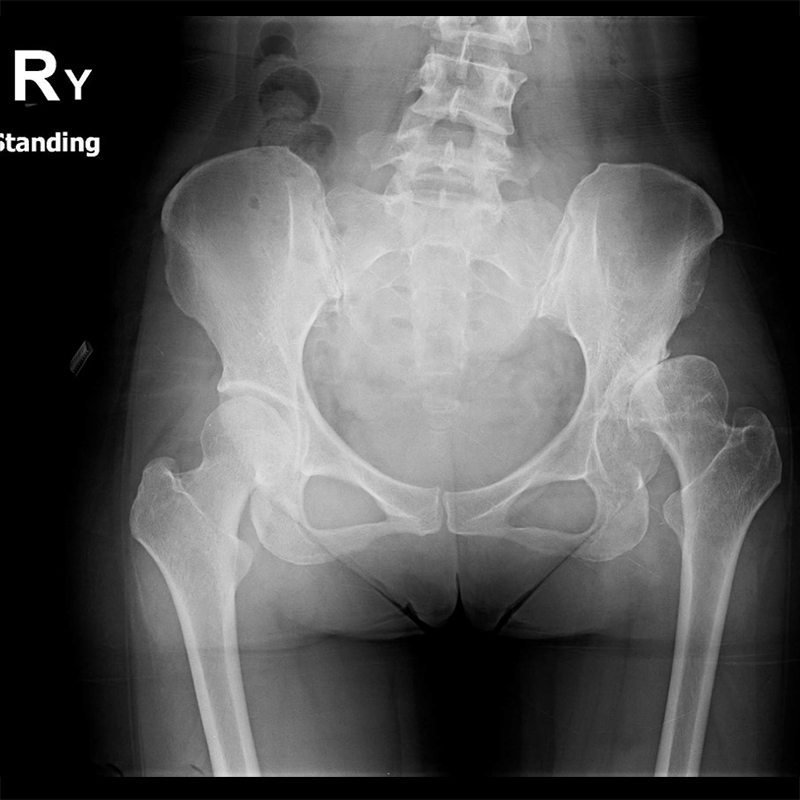

傳統髖關節置換 首頁 案例分享 髖關節手術 傳統髖關節置換 54歲蔡先生退化性關節炎 術前 術後 張女士 51歲 退化性關節炎(DDH先天發育不全 CROWE TYPE 2) 術前 術後 38歲林先生 退化性關節炎 術前 術後 72歲謝女士 退化性關節炎 術前 術後 71歲 謬女士 骨股頭壞死 術前 術後 50歲 郭先生骨股頭壞死 術前 術後 80歲 盧先生骨股頭壞死 術前 術後 林先生 37歲 術前 術後 邱女士 51歲 術前 術後 張女士 50歲 術前 術後